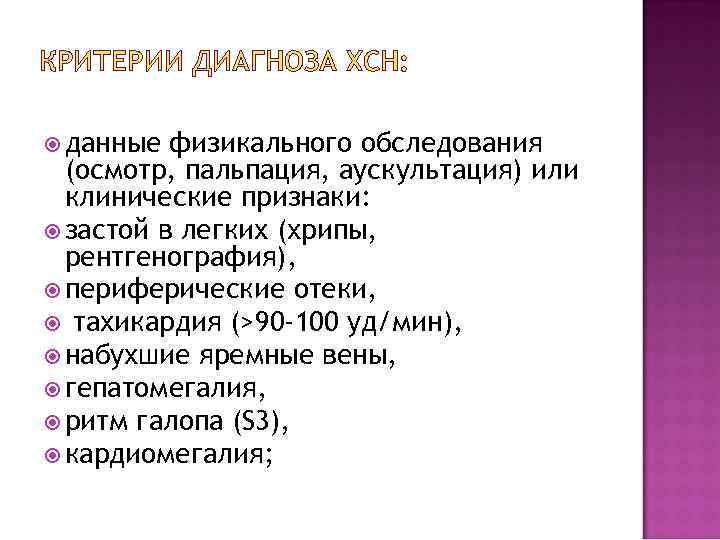

КРИТЕРИИ ДИАГНОЗА ХСН: данные физикального обследования (осмотр, пальпация, аускультация) или клинические признаки: застой в легких (хрипы, рентгенография), периферические отеки, тахикардия (>90 -100 уд/мин), набухшие яремные вены, гепатомегалия, ритм галопа (S 3), кардиомегалия;

КРИТЕРИИ ДИАГНОЗА ХСН: данные физикального обследования (осмотр, пальпация, аускультация) или клинические признаки: застой в легких (хрипы, рентгенография), периферические отеки, тахикардия (>90 -100 уд/мин), набухшие яремные вены, гепатомегалия, ритм галопа (S 3), кардиомегалия;